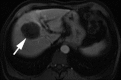

Transcatheter intraarterial therapies have proved valuable in the battle against primary and secondary hepatic malignancies. The unique aspects of all such therapies are their reduced toxicity profiles and highly effective tumor responses. These unique characteristics coupled with their minimally invasive nature provide an attractive therapeutic option in patients who may have previously had few alternatives. The concept of all catheter-based intraarterial therapies is to selectively deliver anticancer treatment to tumor(s). These therapies, which include transarterial embolization, intraarterial chemoinfusion, transarterial chemoembolization with or without drug-eluting beads, and radioembolization with use of yttrium 90, inflict lethal insult to tumors while preserving normal hepatic parenchyma. This is possible because hepatic neoplasms preferentially derive their blood supply from an arterial source while the majority of noncancerous liver is supplied by the portal vein. As part of the interventional oncology review series, in this article we describe the rationale behind each of these transcatheter therapies and provide a review of the existing medical literature.